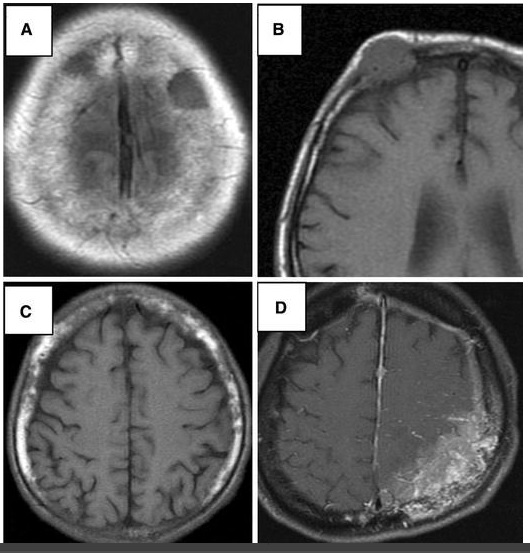

No, dragi mi je rekel, da naj malo poguglam in čeprav prejšnjič nisem našla nič, mi je pa danes na besedi "skull spreading", takoj vrglo ven naslednji strokovni članek z naslovom: "Metastatic skull tumor", v prevodu metastatski tumor lobanje. Prebrala sem, da je v 55% posledica raka na dojkah ter da je možno, da je bolnik brez simptomov. Narisane so tudi skice, kako izgleda in ena izmed opcij je tudi ta:

Fajn. :/ Piše še, da je čas, ki so ga bolniki preživeli od treh do 70 mesecev (preizkavo so delali na 175 bolnikih s tem rakom). Tukaj se ne govori več o možnostih preživetja. Samo koliko časa ti še preostane.